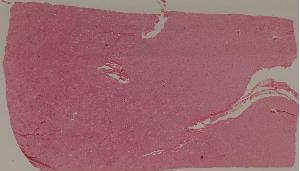

74. Crescentic glomerulonephritis

低倍视野